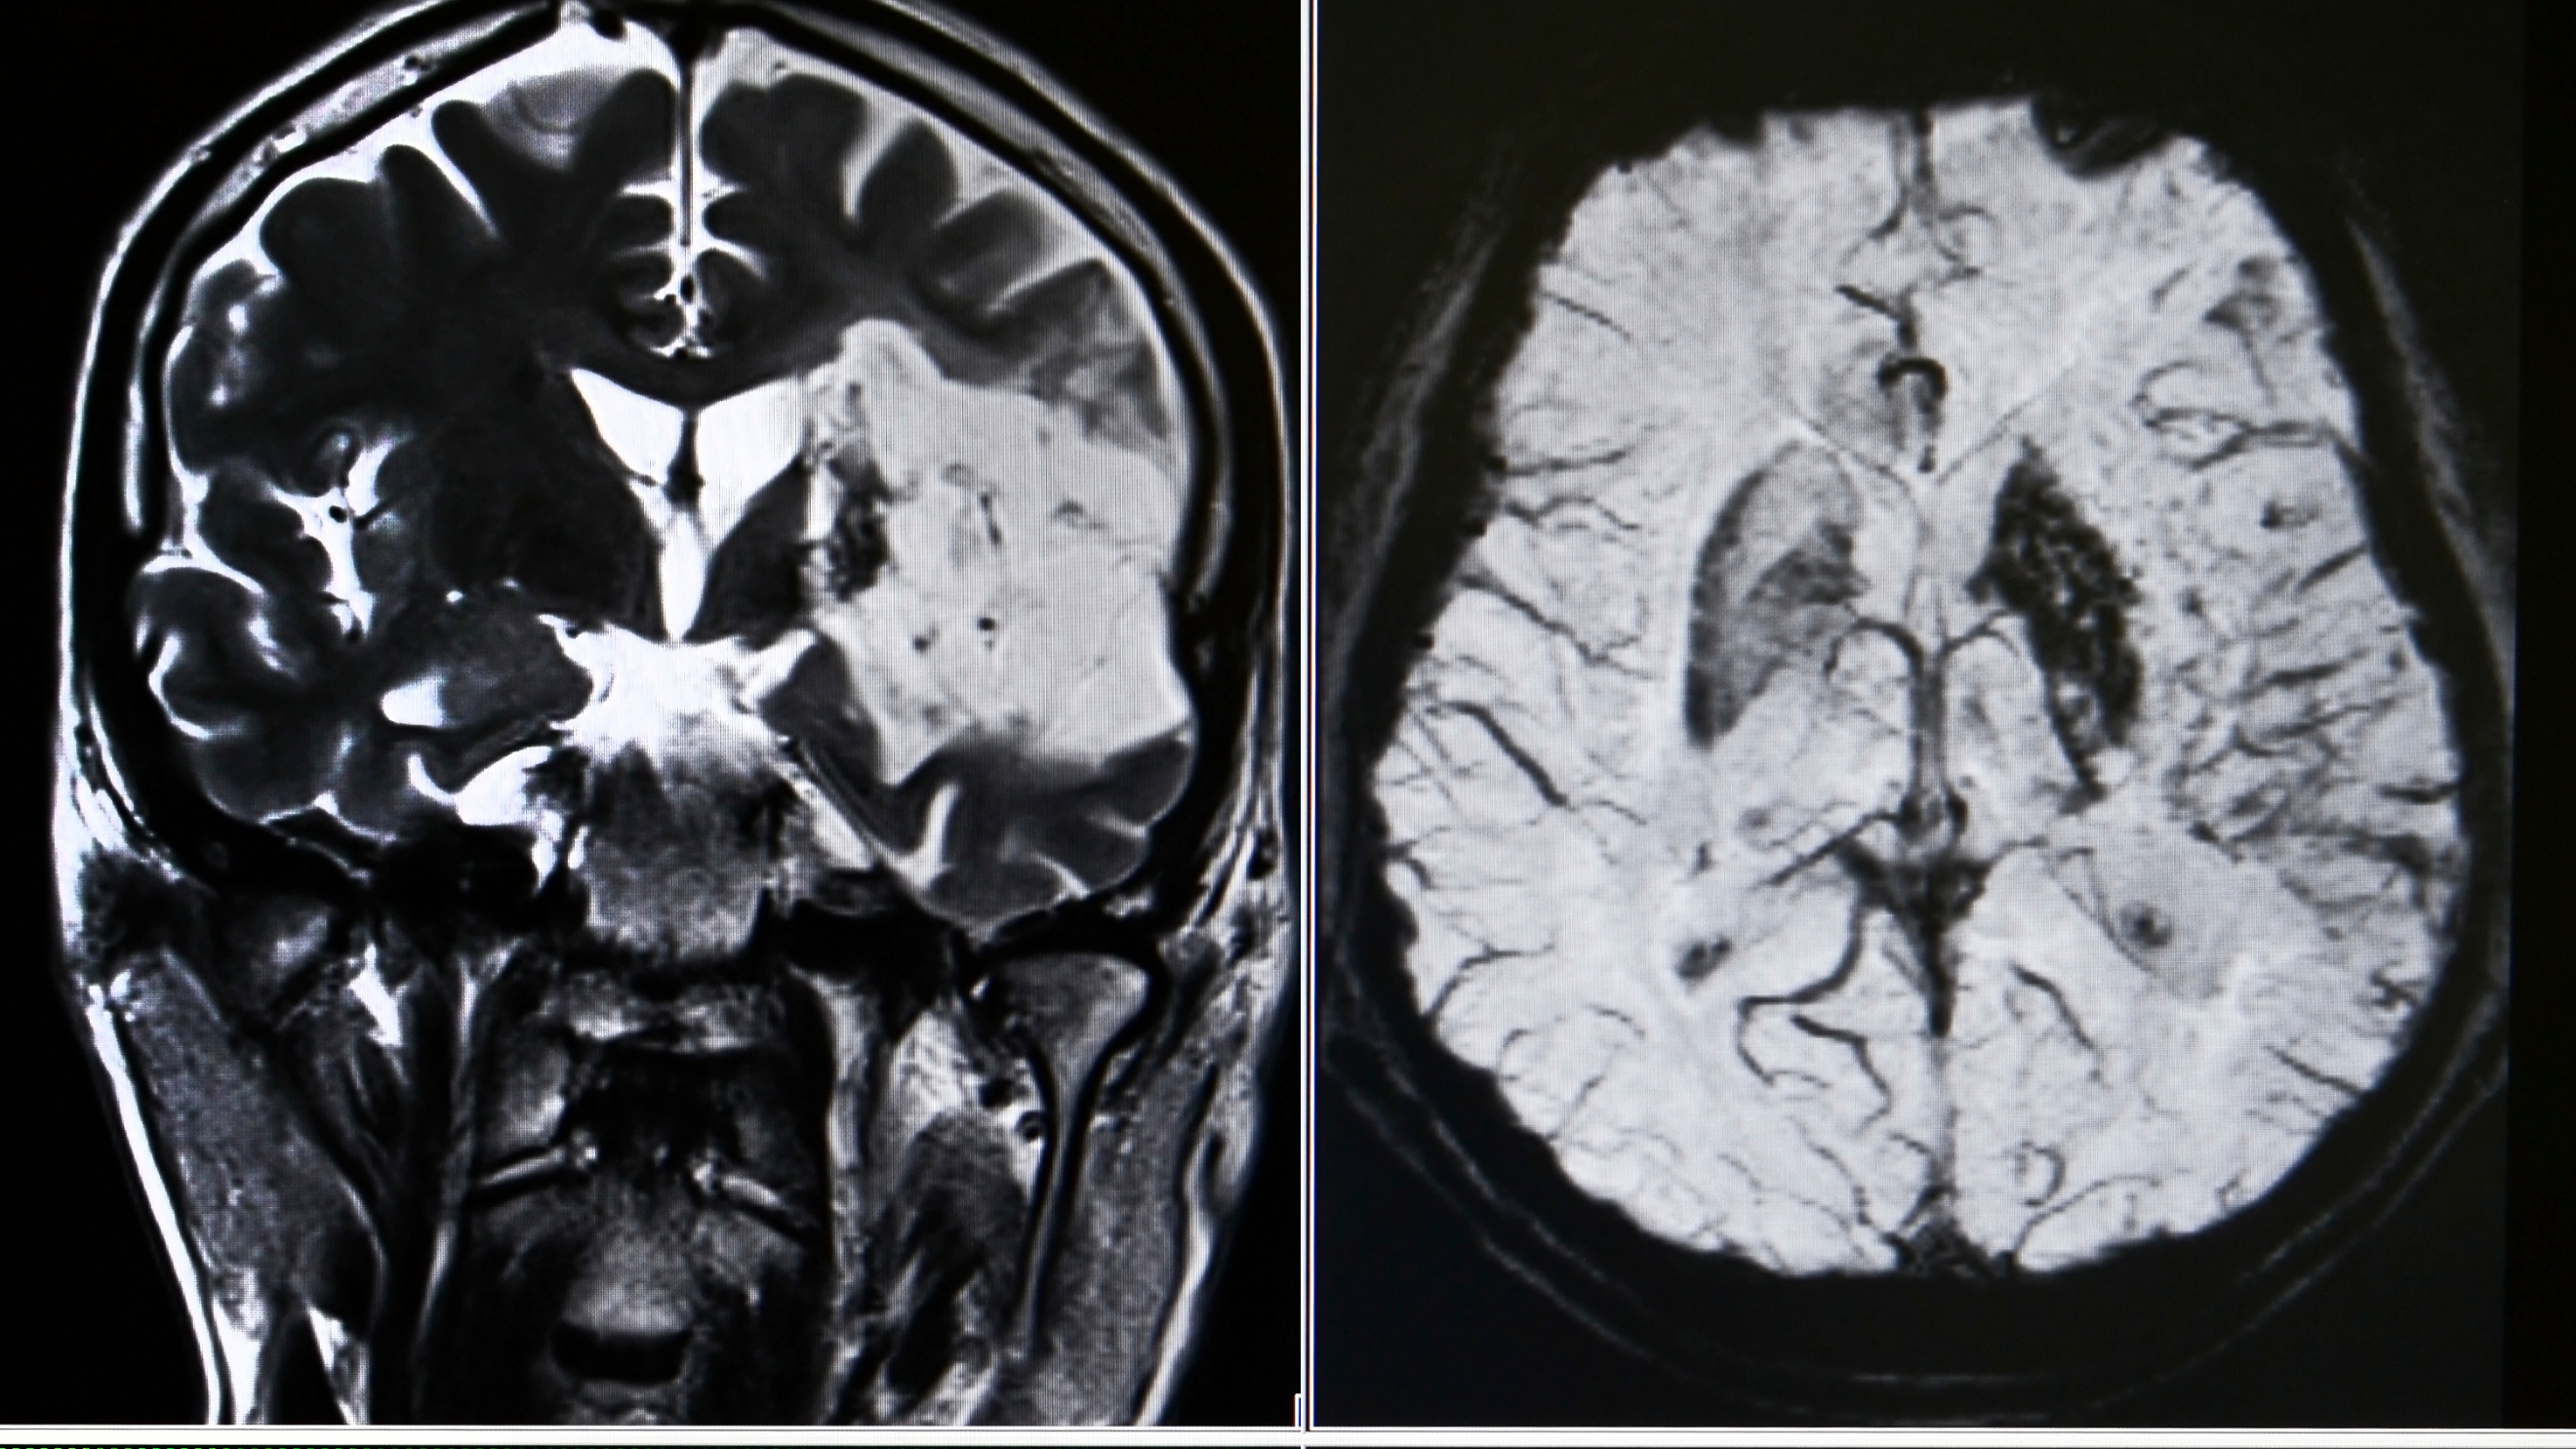

¿Qué es un Accidente Cerebrovascular?

Un ACV ocurre cuando el flujo sanguíneo hacia el cerebro se ve interrumpido, lo que provoca daño en las células cerebrales. Puede ser causado por un bloqueo en los vasos sanguíneos (isquémico) o por una hemorragia cerebral (hemorrágico). La rehabilitación temprana es clave para maximizar la recuperación.

- Electroencefalograma (EEG): Realizamos un mapeo cerebral para identificar las áreas afectadas por el ACV.